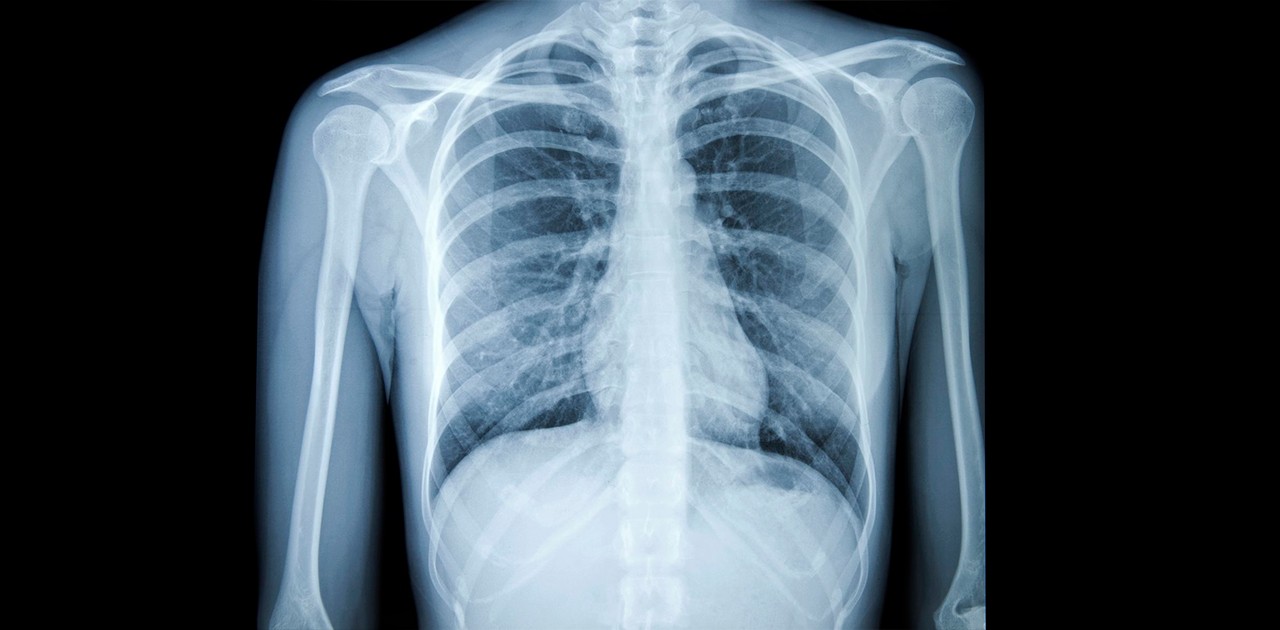

Imagem ilustrativa/Foto: Reprodução/Internet

Entre esses cientistas está um pesquisador da UEM. A equipe descobriu padrões de lesões provocadas pela Covid-19 em pacientes que tiveram pneumonia, analisando exames de raio-x. O método ainda está sendo aperfeiçoado, mas poderá ajudar a confirmar a doença de forma mais rápida.

Eles encontraram padrões nas lesões provocadas pela Covid-19 em pacientes com pneumonia ao analisar exames de raio- x.

Os pesquisadores acreditam que desta forma será possível confirmar a doença com exames de raio-x. Um exame que é mais barato do que uma tomografia e mais acessível nas unidades de saúde.